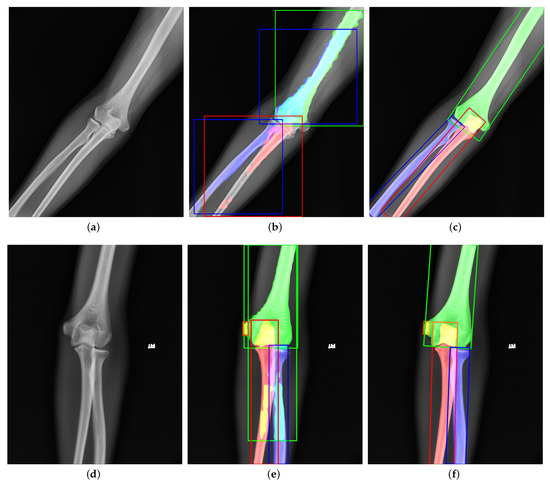

4.6. Visualization Analysis

To compare the effect of network improvement, we take the original image, Mask R-CNN, Ground Truth, and our network together in Figure 11 and Figure 12. According to Figure 11, the third column (Mask R-CNN’s results) shows that horizontal bounding boxes of the ulna and radius are often highly coincident, which leads to poor performance in segmentation. However, the fourth column (our network’s results) obtains a higher precision in bone boundary and correct segmentation results because of the more suitable bounding box and the better segmentation methodology. In addition, the third sample illustrates that the large target bone and the small target bone are often close to each other. The superficial mask branch tends to mistake the tiny target bone for the large and overwhelm the tiny target. The Global-Local Fusion Network can correctly distinguish the pixel classification in the overlapping area of bounding boxes based on the target bone’s information and position information relative to other bones. On the other hand, the radial head is repeatedly detected. With the directional characteristics, the OBBs increase the robustness of multi-scale detection and reduce the possibility of retaining multiple bounding boxes of the same classification.

As shown in Figure 12, the tiny target often hides behind the big target in the anteroposterior pediatric elbow radiographs. The trochlea and ulna often overlap entirely. After adding directional features to each bone, our network can easily detect and segment small targets hidden behind large targets. Moreover, facing the various kinds and serious overlap radiography like in the third sample, Mask R-CNN cannot give a satisfactory answer. With the more suitable bounding boxes and more robust segmentation method, our network reaches the level close to the ground truth.

Figure 11. Visualization of the original image, ground truth, Mask R-CNN’s results, and our network’s results from left to right. Each color corresponds to a bone. The overlapping areas are represented as the addition of overlapping bones’ colors.

Figure 12. Another visualization of the original image, ground truth, Mask R-CNN’s result, and our network’s result from left to right.